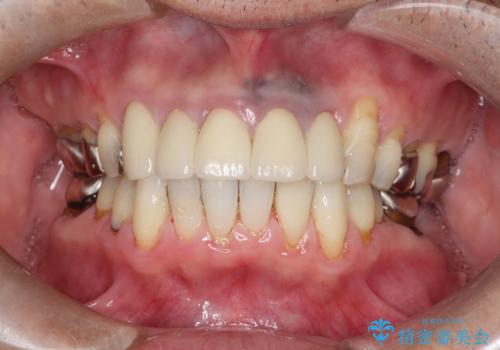

[フルジルコニアクラウン] 老朽化した銀歯を白く